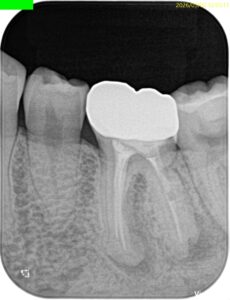

Pre-op Endo test(2026.3.2)

頬側遠心のクラウンマージン部付近にアブセスがある。

2枚のPAでは何もわからない。

診断はついたが、

あなたはこの一連の“絵”に気づいただろうか?

この歯は歯頸部に外部吸収を抱えていたのである。

この2枚のPAでそれがわかるだろうか?

私にはわからない。

穿孔しているのだろうか?とまず思ったが、CBCTをみてそれは穿孔でなく外部吸収の可能性が高いと判断できた。